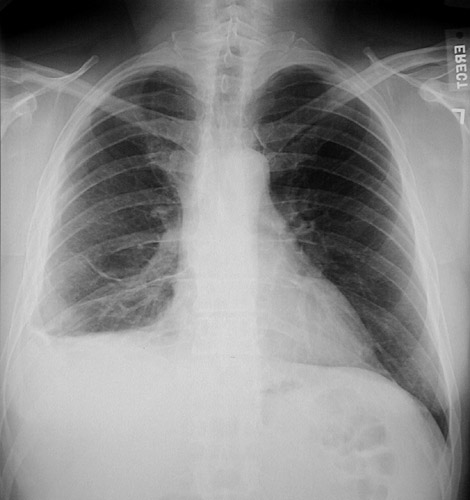

This chest radiograph shows a right pleural mass that is characterized by pleural thickening, volume loss of the right lower lobe, and obscuration of the diaphragmatic dome.